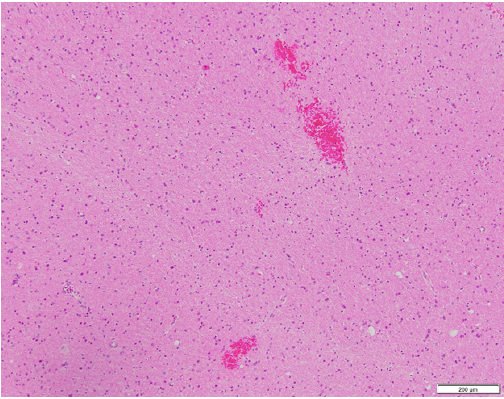

7-year-old boy presented with acute weakness following a gastrointestinal illness. Exam was notable for flaccid quadriparesis, hyporeflexia without encephalopathy. He received IVIG for presumed Guillain Barre syndrome. Initial CSF analysis and MRI Brain/spine were unremarkable except high CSF lactate of 2.9. A week later, he became less responsive, had autonomic fluctuations, lost gag reflex, and got intubated. Repeat MRI Brain showed new bilateral (L>R) cortical, subcortical and brainstem lesions as seen in Figures 1A, 1B & 1C. Serial MRI brain showed fast developing multiple lesions involving the white and gray brain matter with areas of restricted diffusion. Repeat CSF analysis including encephalopathy/ multiple sclerosis panel were unremarkable. Biopsy of left frontal lesion showed vasculitis with lymphocytic infiltration and areas of small hemorrhage with no necrosis as shown in Figures 2A & 2B. He had no response to 7 days of IV steroids or IVIG. Cyclophosphamide therapy was started for presumed CNS vasculitis and mitochondrial cocktail for high serum/CSF lactate though rest of the mitochondrial labs returned negative. Infectious work up for Aspergillus, hepatitis B&C, Bartonellosis, Lyme, Tuberculosis and HIV were negative. Investigation for Immune-mediated encephalopathy were negative for antibodies to AMPA-R, Amphiphysin, AGNA-1 to 3, CASPR2, CRMP-5, DPPX, GABA-B-R, GAD65, GFAP, LGI1, mGluR1, NMDA-R, PCA-Tr, PCA-1 & 2 in CSF and serum except mildly elevated serum anti-GAD65 (0.09 with normal <0.02). MRA head/neck and CT abdomen/chest/pelvis negative for evidence of vasculitis or mass. Two weeks later, he developed right sided focal seizures which responded to Levetiracetam, Lacosamide and Epidiolex. Whole exome sequencing confirmed pathogenic mutation for Pyruvate Dehydrogenase A1 deficiency (PDHA1). Now, 4 months later, his encephalopathy has resolved, strength and walking are improving with physical therapy.